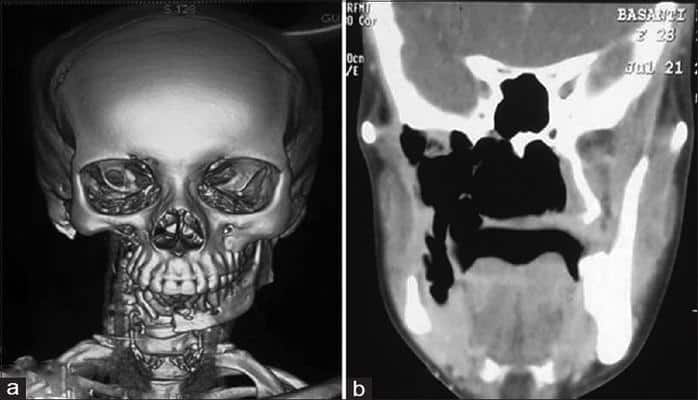

С 1954 года в истории медицины было зафиксировано всего 64 случая синдрома исчезающих костей и большинство из них поражали кости рук. В сети можно найти еще более редкие аномалии, когда синдром поражал кости черепа, в том числе нижнюю челюсть.